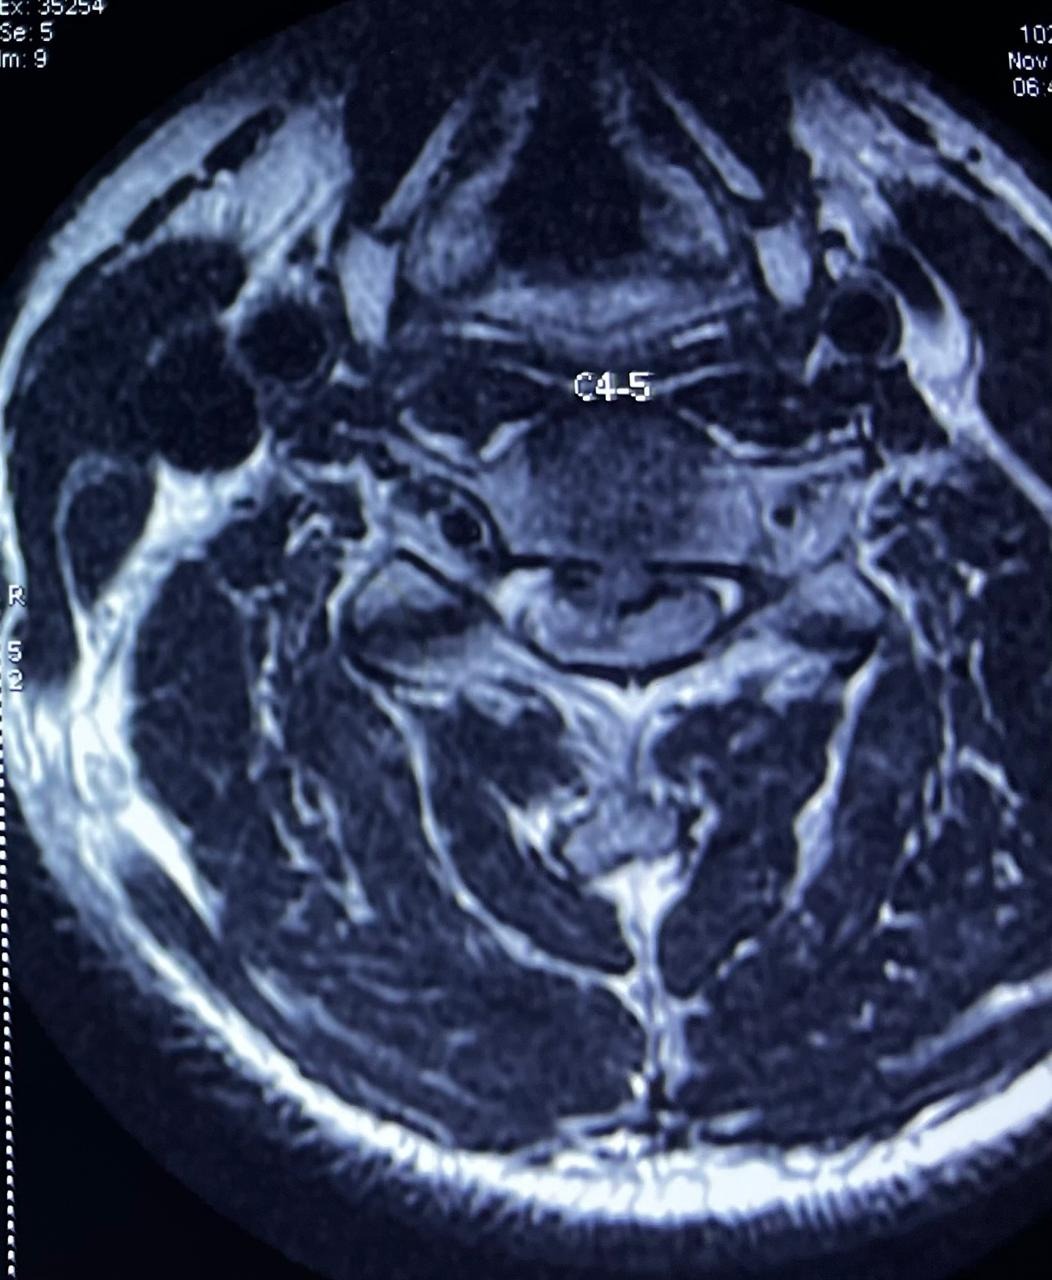

Most spine surgeries are not emergencies and can be safely planned after proper evaluation and imaging.

Modern spine surgery has become much safer due to advances in surgical techniques, better imaging, improved anesthesia, and enhanced perioperative care. Many procedures today are minimally invasive, which means smaller incisions, less tissue damage, and faster recovery.

Many spine surgeries today are minimally invasive, involving smaller incisions, less muscle damage, shorter hospital stays, and faster recovery.